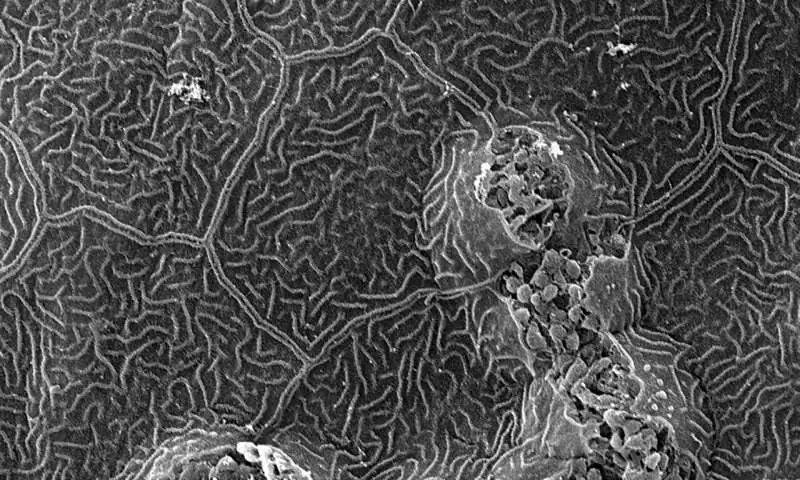

斑马鱼皮肤区域的显微照片 图片来源:布里斯托大学

一项发表在《Cell Reports》上的新研究首次在斑马鱼中观察到炎症细胞利用基底膜区的细胞外基质屏障层中的弱点或微穿孔进入皮肤癌细胞。

为了进入癌细胞,免疫细胞需要首先破坏组织间的细胞外基质屏障层—基底膜区。研究人员观察到炎症细胞利用基底膜区的薄弱环节作为接近癌症的简便途径。那些离薄弱环节最近的癌细胞克隆往往会受到更多的炎症细胞的侵袭,因此它们生长得更快。

这项研究的发现与癌症患者有着明确的临床相关性,因为基底膜区域的微穿孔已被证明在人类的呼吸道和肠道发生,因此可以作为类似的窗口,让炎症细胞进入癌症。